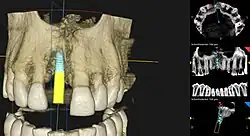

Planung

Die Planung einer Implantation geschieht je nach Komplexität der Situation mittels eines einfachen Zahnröntgens, oder durch Zuhilfenahme weiterer Hilfsmittel. Mit Hilfe einer Computertomographie (CT) oder einer Digitalen Volumentomographie (DVT) kann die Position des Implantats vor dem Eingriff festgelegt werden. Die Planung erfolgt dreidimensional am Computer und wird anhand einer individuell hergestellten Bohrschablone umgesetzt.[42] Nachteilig hierbei sind die Strahlenbelastung und die zusätzlichen Kosten für den Patienten.

Backward-Plannings

Beim Backward-Planning geht die Planung der Implantation nicht von der Kiefer- und Knochensituation aus, sondern vom Zahnersatz. Die Position der Implantate richtet sich sozusagen rückwärts nach der Stellung der neuen implantatgetragenen Zähne. Aufgrund von Abformungen und dreidimensionalen Bilddaten entwickelt das Zahnlabor ein Modell des späteren Zahnersatzes. Anhand dieses Modells ermittelt der Implantologe – mit computergestützter 3D-Implantatplanung – die geeignete Zahl, Position, Länge, Ausrichtung und Bohrtiefe für die Implantate. Auch hier wird die individuelle Knochen- und Weichteilsituation berücksichtigt.[42]

Per Bohrschablone wird für eine präzise Platzierung die digitale Simulation in den Mund übertragen.